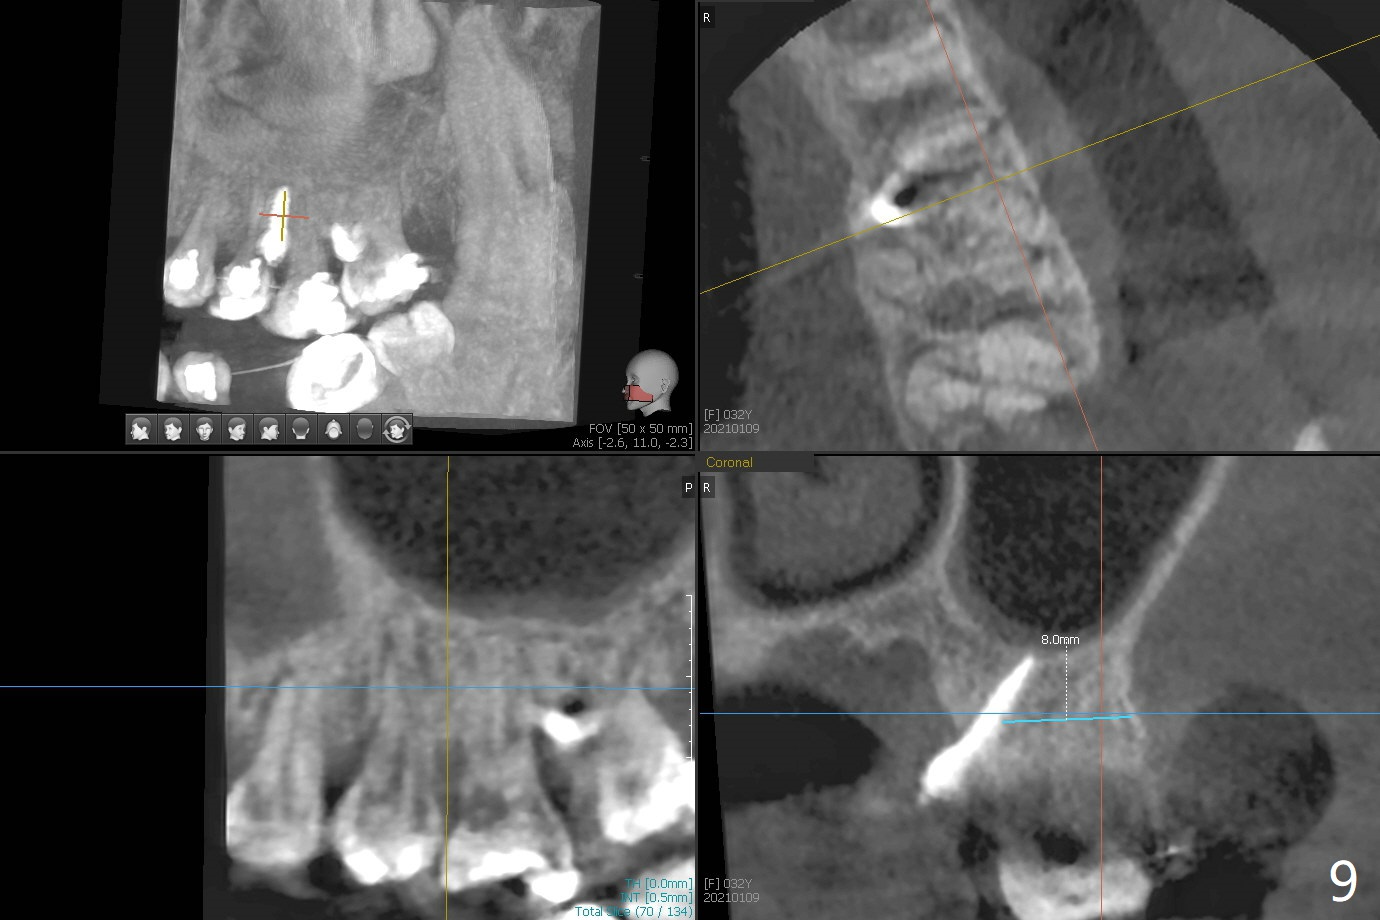

矫正器放置后一个月,正好有充裕时间,匆忙研究全景片(最好CT),好像左上6近中间隙大,近中颊侧,远中腭侧似乎是种植位点(图一:白圆圈),植入越高越宽,不容易伤及邻牙牙根。但是微型植体种植原则是必须种植在角化龈,减少炎症(以前不明白为什么)。当植体在移动牙龈植入时(图二:白箭头),牙龈浮起来,估计非角化牙龈也不能与植体产生紧密结合。取出后,完全可以在6近中颊侧角化龈植入,但是仔细检查发现远中颊侧角化龈更宽,所以在那里扎根(图二:黑箭头),因此腭侧就得选择近中(图三)。微型植体可以即刻使用,power chains常滑脱,压迫牙龈,在这个病例很可能进入远中牙间隙,所以需要在远中边缘嵴加树脂(图四,五:* (1.6x8mm))。第二天远中颊侧植体松动,取出后,插入2x10毫米一段式植体,仍然松动(图六)。CT显示植体下缘穿破牙槽骨(图七,骨质吸收严重与图八近中牙槽骨高度对比)。如果在近中颊侧重新植入微型植体,必须使用6毫米长植体(图九),所以最好在远中颊侧重新植入(图十:红色),缺损区(黑色)植骨。在使用14 niti时,左下7松动,病人同意拔除8,以后后推7,然后6种植(图十一:(左上8已拔除(x))),同时左上6远中植骨,左下8远中牙槽窝放置浸泡PRF液体胶原塞(图十二:1),近中牙槽窝粘性骨粉(2),最后牙槽窝上部PRF膜(3),PGA缝线。可能需要Cytoplast。